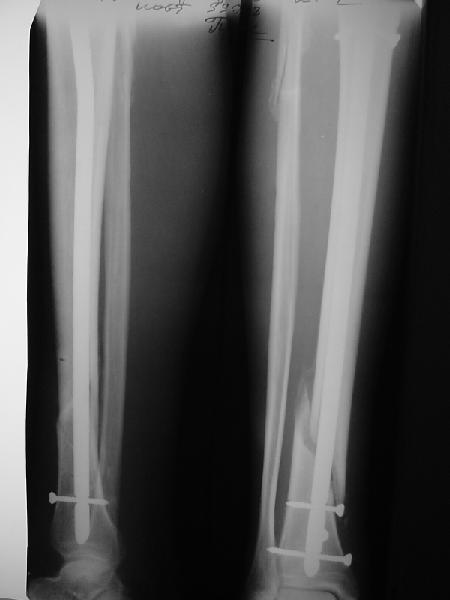

Как мне показать пример? Фото стоящего на одной оперированной конечности пациента? O! Пример, подвигнувший нас на некоторое изменение технологий. Пациент этот ходил с полной нагрузкой вопреки рекомендациям. В качестве подтверждения - сломанный проксимальный статический винт к 1 мес., а к 2 мес. - все остальные. Сейчас мы перешли на более fool-proof остесинтез.

На мой взгляд, на снимках, приведённых Вами - неправильно сростающийся перелом дистальной трети большеберцовой кости, состояние после остеосинтеза интрамедуллярным гвоздём.

Как Вы пишите снимок под номером 1 - менсяц после операции, под номером 2- два месяца после операции.

Ok. А также и следующий, в 3 месяца.